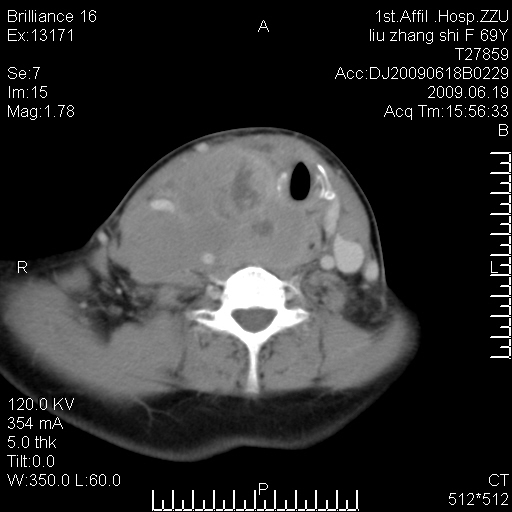

标题: CT26782:女,69岁,颈部占位,3天后公布病理结果。

【病理证实系列】女,69岁,颈部占位,有病理结果,3天后公布。(由于病例时间较久,临床资料不全,请网友见谅)本系列将有几百种常见、少见及罕见病例,均经病理证实。病例资料来自郑州大学第一附属医院。与网友共享,本人有空就发。

甲状腺癌并颈部淋巴结转移。感谢楼主的良苦用心,谢谢。

甲状腺癌并颈部淋巴结转移。

需与鼻咽癌鉴别!

支持甲状腺癌广泛侵及周围结构并颈部淋巴结转移。

鉴别:淋巴瘤、恶性神经源性病变、恶性纤维组织细胞瘤。

病理结果:颈部非霍奇金淋巴瘤。

右侧甲状腺确实有问题